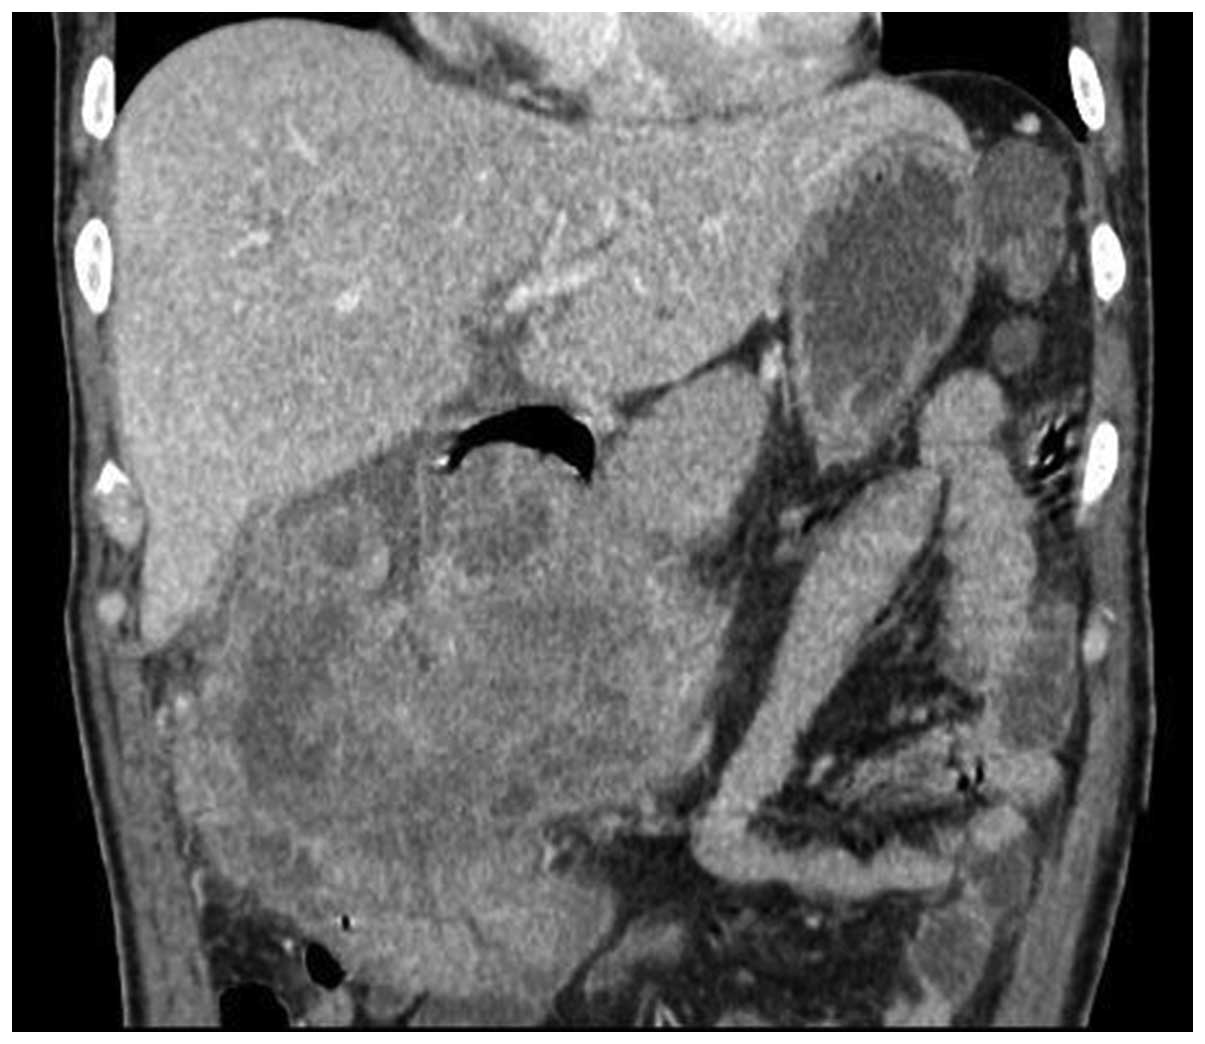

A 49-year-old Chinese male with melena, anemia and fatigue visited the Emergency Room at Ren Ji Hospital Affiliated to Shanghai Jiao Tong University School of Medicine (Shanghai, China), on July 22, 2013. The proband's hemoglobin was 39 g/l upon entering the ward. Abdominal ultrasonography revealed a mass with mixed echogenicity in the right upper quadrant of the abdomen. A computed tomography (CT) scan revealed a 14 cm-diameter mass in the gastric antrum and gastric body, which infiltrated the serosa of the stomach. The gallbladder and hepatic flexure of the colon were also involved. CT contrast enhancement was evident in the two lesions (Figs. 1 and 2). A positron emission tomography (PET)-CT scan revealed a large irregular mass with abnormally high fluorodeoxyglucose (FDG) metabolism in the region of the distal stomach, gallbladder fossa and hepatic tissue in the vicinity (Fig. 3). A lymph node with high FDG metabolism was observed in the region of the pancreatic head (Fig. 4). Endoscopic investigation of the upper gastrointestinal tract identified an irregularly shaped lesion on the gastric antrum and body (Fig. 5). The histopathological section of the endoscopic biopsy revealed that the majority of the tumor cells were spindle shaped in morphology. Following a primary diagnosis of gastric malignancy, the patient received surgery on August 3, 2013. A 14×13×8 cm, solid mass with an irregular surface was identified during surgery. In addition, the No. 13 lymph nodes were markedly enlarged and fused, measuring 20×35 mm. The distal stomach, gallbladder and right hemicolon were resected in order to completely remove the tumor. In addition, an extended D2 lymphadenectomy was also performed. Reconstruction was conducted with the gastrojejunum Roux-en-Y anastomosis (7). Histopathological diagnosis was as follows: Sarcomatoid carcinoma of the gastric antrum and body (14×13×8 cm in size, with serosa invasion), the gallbladder and adjacent colon wall were also involved and No. 13 lymph node metastasis was observed.